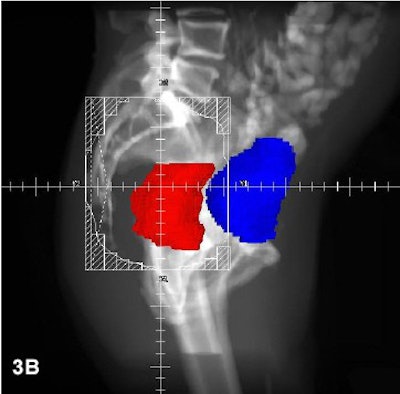

Three radiation fields (PA with right and left lateral) were used for all patients, using CT-based 3-D treatment planning. Rectum is red; bladder is blue.